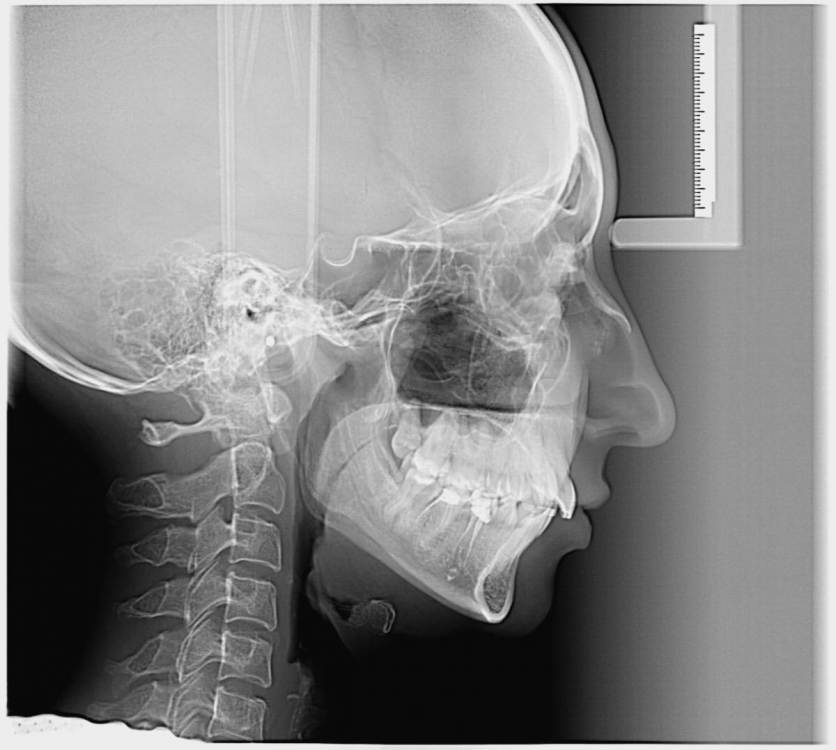

Добрый день.Обратилась к ортодонту

беспокоить начал сустав с права ,сказали заняться лечением ,удаление 8

в данный момент занимаюсь лечением зубов и сказал доктор перед брекетами ставить капу,

но сейчас чувствую что сустав не болит и не хрустит.можно ли сначало брекеты а потом капа

Если есть - ТРГ и фото гипсовых моделей челюстей.